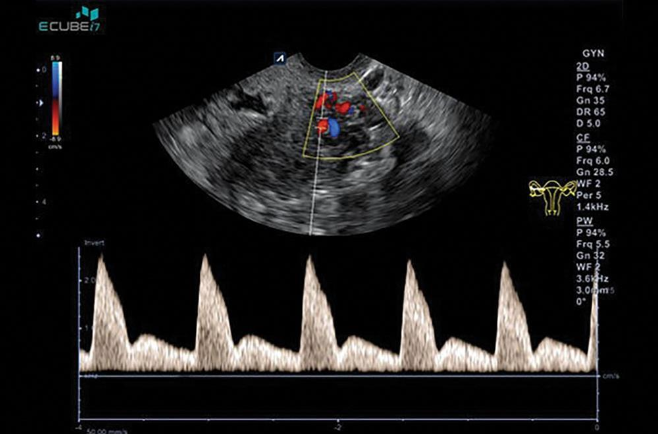

_____________is used to evaluate the resistive index (RI = peak systolic

− end diastolic/peak systolic) or pulsatility index (PI = peak systolic −

end diastolic/mean).

Pulsed Doppler

_____________(RI less than 0.4) has been found in patients with

endometrial carcinoma

Low Resistance flow

______________-(RI greater than 0.5) in normal or benign endometria.

High resistance flow